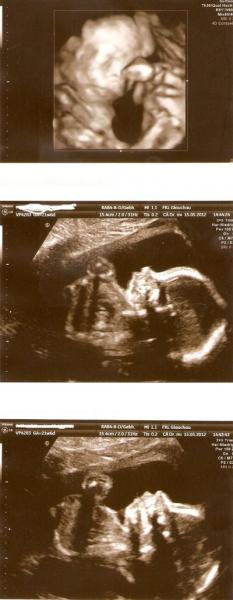

Hallo, wir waren heute das zweite mal zur FD, insbesondere der Kontrolle des Herzens. Wir sind unheimlich erleichtert, denn es ist alles soweit io, war wieder total schön krümelchen zu beobachten und als sie mit dem Doppler die Herztöne dargestellt hat, musste ich ein paar Tränen lassen... Hach, ich bin so verliebt in das kleine Wesen. Und ist auch witzig die boxende Hand über den Bildschirm zu beobachten und es zu spüren. Hier die Bilder.

Bild zu zurück von FD - Forum für September - Mamis